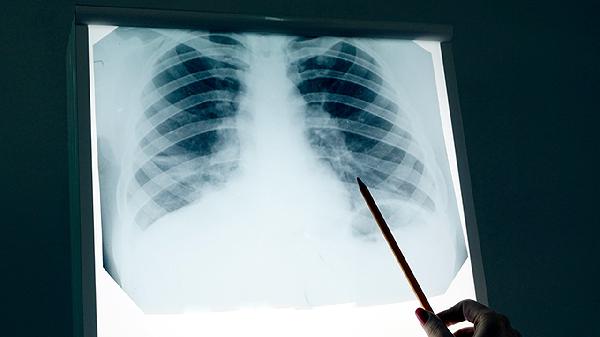

肺癌属于恶性肿瘤,治疗需根据病理类型、分期制定个体化方案。早期患者以手术根治为主,中晚期需结合放化疗、靶向治疗或免疫治疗。中药辅助治疗时,必须由肿瘤科与中医科医师联合评估,监测肝肾功能及药物不良反应。患者切勿自行用药或中断规范治疗,以免延误病情。